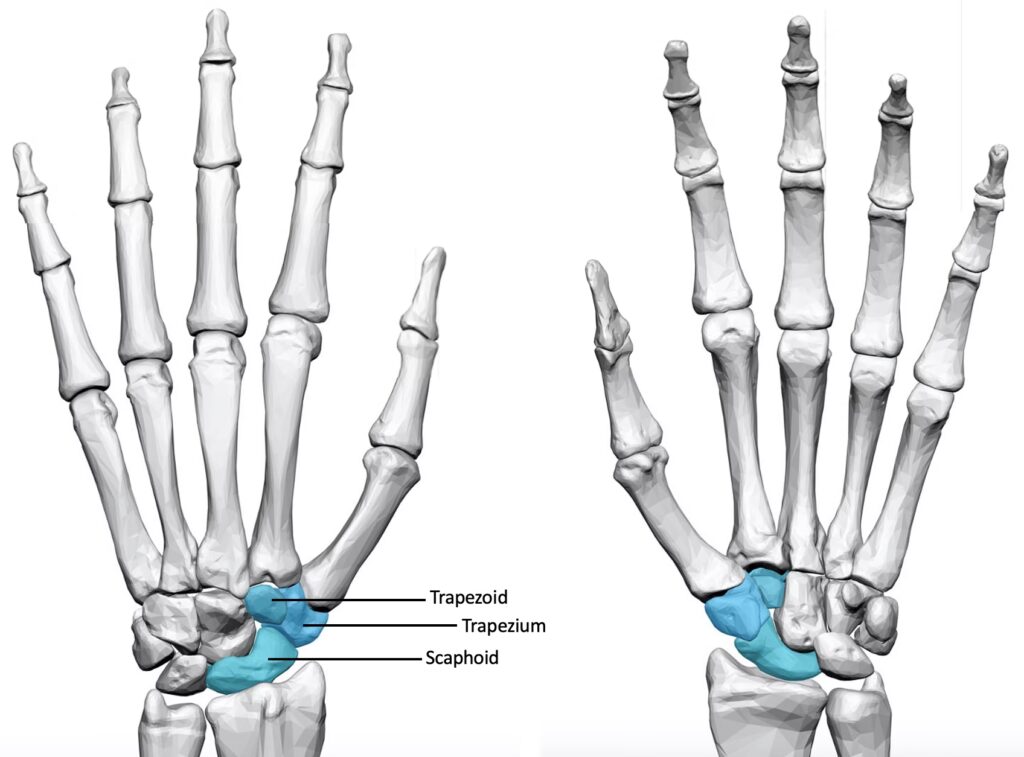

For at forstå STT-artrose er det nødvendigt at kigge nærmere på håndleddets komplekse opbygning. Navnet "STT" er en forkortelse for de tre håndrodsknogler, der danner leddet: Scaphoideum (bådbenet), Trapezium (det store mangekantede ben) og Trapezoideum (det lille mangekantede ben). Samspillet mellem disse tre knogler er unikt og afgørende for håndleddets bevægelighed og stabilitet, men det er også dette samspil, der gør leddet sårbart over for slidgigt.

- Scaphoideum (Bådbenet): Denne knogle har en karakteristisk form, der minder om en nyrebønne eller en cashewnød. Bådbenet fungerer som et afgørende bindeled mellem den proksimale og distale række af håndrodsknogler. Den er næsten fuldstændigt dækket af brusk og artikulerer med hele fem andre knogler, herunder spolebenet i underarmen samt trapez-knoglerne. Stærke ledbånd holder bådbenet på plads, men knoglen er berygtet for sin skrøbelige blodforsyning, der kommer "bagfra" (retrograd blodforsyning). Dette gør den sårbar over for knoglebrud og efterfølgende komplikationer som avaskulær nekrose (knogledød).

- Trapezium (Det store mangekantede ben): Denne knogle er placeret ved bunden af tommelfingeren. Dens vigtigste ledflade er den distale, sadelformede flade, der danner led med tommelfingerens mellemhåndsknogle (metakarp). Dette sadelled er årsagen til tommelfingerens fantastiske bevægelighed i flere planer. Opadtil (proksimalt) danner trapezium led med bådbenet, og det er her, en del af STT-leddet findes. Bevægeligheden i dette led er langt mindre end i tommelfingerens grundled.

- Trapezoideum (Det lille mangekantede ben): Denne mindre knogle ligger ved siden af trapezium og danner også led med bådbenet. Den har en mere begrænset rolle, men er en integreret del af STT-ledkomplekset.